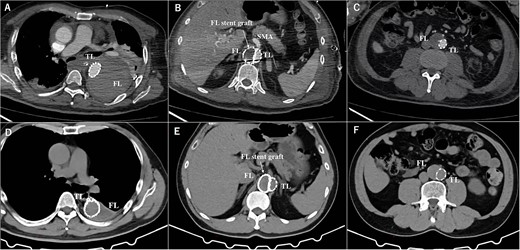

The postoperative contrasted computed tomography at thoracic level (A), at SMA level (B), at abdominal level (C). The computed tomography three years after the operation at thoracic level (D), at SMA level (E), at abdominal level (F). TL: true lumen FL: false lumen RA: renal artery CA: celiac artery SMA: superior mesenteric artery CIA: common iliac artery.